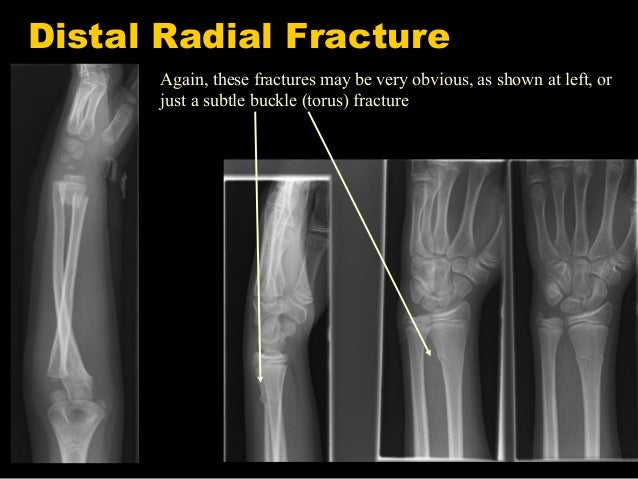

īuckle fractures are stable and do not require follow-up. On average, the complete fractures displaced 9 degrees. Usually, the wrist is X-rayed in 2 planes as. The greenstick fractures displaced 5 degrees on average, and continued to displace after the first 2 weeks. Distal radius and forearm fractures are injuries that are frequently seen in trauma surgery outpatient clinics. Surgical intervention is indicated for significantly displaced or angulated fractures in. Treatment is closed reduction and casting for the majority of fractures. Diagnosis is made with plain radiographs of the forearm. The lateral angulation of the buckle fractures did not change importantly throughout the treatment. Both Bone Forearm Fractures are one of the most common pediatric fractures, estimated around 40 of all pediatric fractures. The greenstick fractures had more complications than the buckle fractures. Only 1 of 311 follow-ups led to an active intervention. The fracture type was determined from the initial radiographs and the angulation on the lateral films was noted. The medical records of 305 distal radius fractures in patients aged less than 16 years treated at our institution in 2006 were reviewed, and any complications were noted. The stability of greenstick and buckle fractures of the distal radius was assessed by comparing the lateral angulation radiographically. We investigated the degree to which the follow-up visits reveal complications and lead to change in management. 163 Video/Pods 30 Techniques 4 4.5 ( 165 ) 68 Topic Podcast Images Summary Distal radius fractures are the most common orthopaedic injury and generally result from fall on an outstretched hand. this review has found that angular displacement after the application of a cast occurs less often when the forearm is immobilised in the supinated position.Numerous follow-up visits for wrist fractures in children are performed without therapeutic consequences. treatment is with the application of a plaster of Paris cast. Relevant Paper(s) Author, date and countryĦ0 children, 20 randomly allocated to each groupĪngular displacement greatest in pronation group and least in the supination groupįracure of the distal radius is a common injury in children.

treatment is with the application of a plaster of Paris cast, but in which position should the forearm be immobilised (pronated, neutral or supinated)ġ citation which was a high quality randomised control trial radiology confirms a greenstick fracture of the distal radius. In with should Clinical ScenarioĪn eight year old child presents to the emergency department with a suspected wrist fracture.